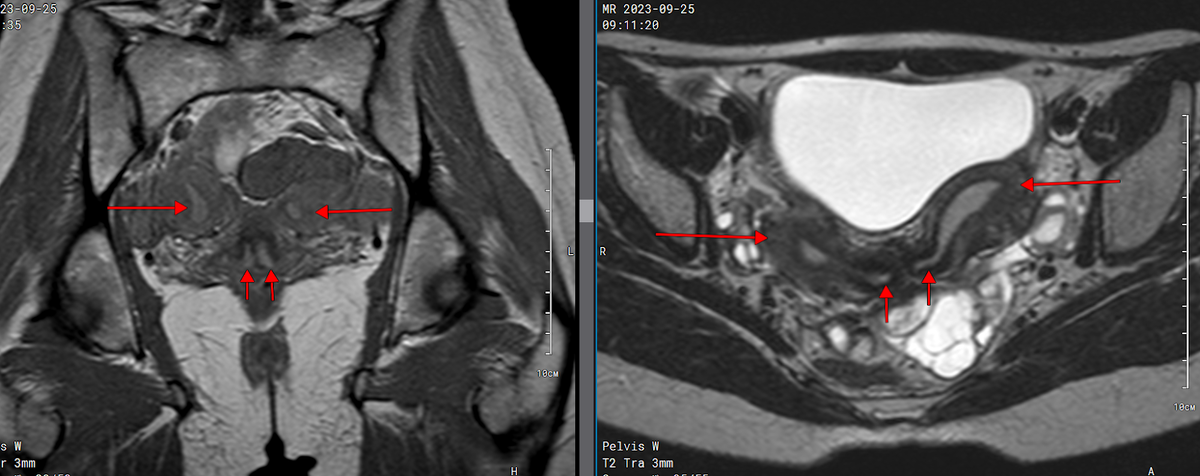

Отмечается аномалия развития в виде удвоения тела матки и наличия полной перегородки шейки матки. Функциональный эндометрий хорошо дифференцируется, дупликатура толщиной до 0,6 см в правом роге, до 0,7 см в левом роге. Переходный слой достаточно симметричный с обеих сторон, максимальной толщиной до 0,4 см (норма до 1,0 см). Шейка матки имеет полную перегородку, стенки не утолщены, имеют дифференцированно зональное строение. Цервикальные каналы не расширены.

Рис.1. Т1 корональная и Т2 аксиальная плоскости; длинными стрелками указаны правый и левый рога матки.